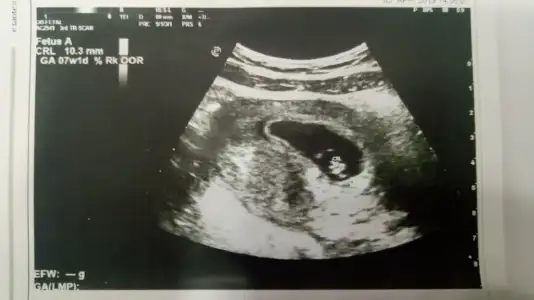

bugün 7+3 olduk canım 8. haftanın içindeyiz çok şükür. valla ben hala kollu bacaklı bir bebek görüntüsü göremiyorum ultrason kağıdımda :-) hatta eşim de gidiyoruz geliyoruz çocuk hala 1 cm nasıl büyüyecek bu diyor :KK70: doktorda birşey söylemedi sanırım beklediğim görüntü için henüz erken, bir sonraki randevuya 1 ay sonra gelirsin dedi 11 haftalık olacağız o zaman kolunu da görürüm bacağını da diye düşünüyorum :KK36: sen nasılsın ne kadarlık oldunuz

:) eşin güzel söylemiş zaman geçmiyor sanki bana da büyümüyorlarmış gibi geliyor. ben en son 7+1 ken gitmiştim yani geçen hafta dr bu hafta elleri kolları ayakları oluşacak demişti açıkcası merak ediyorum ne durumda diye , bizde bugün 8+4 olduk bizde 9. haftanın içindeyiz o halde bir sonraki randevum ayın 15 inde çok heyecanlıyım :) allah korktugumuza uğratmasın

bende ilk önce aynı şeyi sormuştum kalbi atıyor mu ilk onu söyleyin demiştim, şükür ki atıyordu inşallahta atmaya devam ediyordur. canım senin usg görüntünle bide bi üstte yeni usg görüntüsü atan arkadaşa baktım benimki sizinkilerden çok farklı neden ki anlamadım gitti , yani duruş ve yapı olarak farklı sizin ki yuvarlak gibi benim ki salatalık gibi :)

aa evet sanki ayakta dik duruyor gibi :) canım bence bunda korkulcak bişey yoktur ki olsa doktorun söylerdi mutlaka banada bu sefer kesemin şekli çok ilginç geldi yamulmuş bişeyler olmuş sanki :) ilk görüntümde yusyuvarlaktı halbuki. bu arada kesenin sağında olursa kız solunda olursa erkek diyorlar seninki de sağ tarafta gibi aslında :)